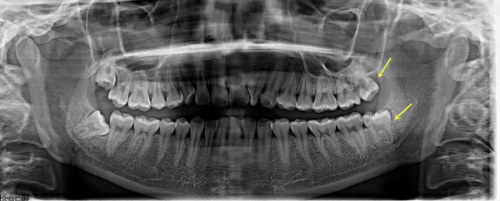

北京青苗口腔门诊部位于北京市海淀区火器营路 1 号院 1 号楼 128 - 129 室,一直致力于为患者提供高质量的口腔医疗服务。医院配备了精良的口腔诊疗设备,像数字化 X 光机、口腔内窥镜及激光治疗仪器,这些设备能够确保为患者提供精细的诊断与治疗。该门诊部提供牙齿洁治、牙齿矫正、种植牙、拔牙及口腔修复等多项口腔健康服务,满足患者不同的口腔需求。

特别多患者在 孙婧婧 医生的治疗下,牙齿状况得到了极大改善。通过 北京青苗口腔门诊部孙婧婧做的前后对比图 可以看到,原本参差不齐的牙齿变得整齐美观,面部轮廓也因牙齿的矫正变得更加协调。这些显著的成效足以证明孙医生的技术实力。www.haohanprint.com